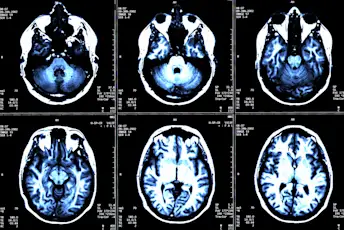

MS病变如何表格?

对于我们的MINI MED学校视频系列,我们分解了MS如何损害身体的神经并导致其最常见的症状。